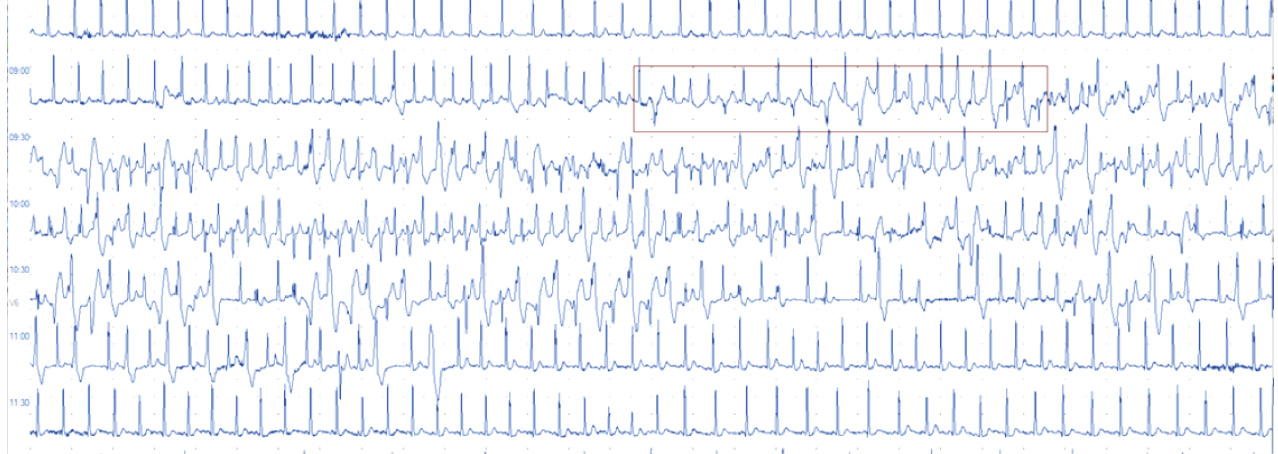

Из анамнеза известно, что у двух братьев (пациент 1 и пациент 2) манифестация заболевания произошла в возрасте 3 лет в виде синкопального состояния во время физической нагрузки. Диагноз установлен на основании данных ХМ-ЭКГ, где была зарегистрирована нагрузочная двунаправленная желудочковая тахикардия (рис. 1).

Рис. 1. Фрагмент холтеровского мониторирования электрокардиограммы: на фоне синусовой тахикардии с частотой сердечных сокращений 121 уд/мин регистрируется полиморфная желудочковая экстрасистолия, переходящая в полиморфную желудочковую тахикардию (начало эпизода выделено красной рамкой), с последующим развитием двунаправленной желудочковой тахикардии длительностью 6 секунд; затем двунаправленная желудочковая тахикардия купируется и регистрируется желудочковая экстрасистолия по типу бигеминии и восстановление синусового ритма с частотой сердечных сокращений 100 уд/мин